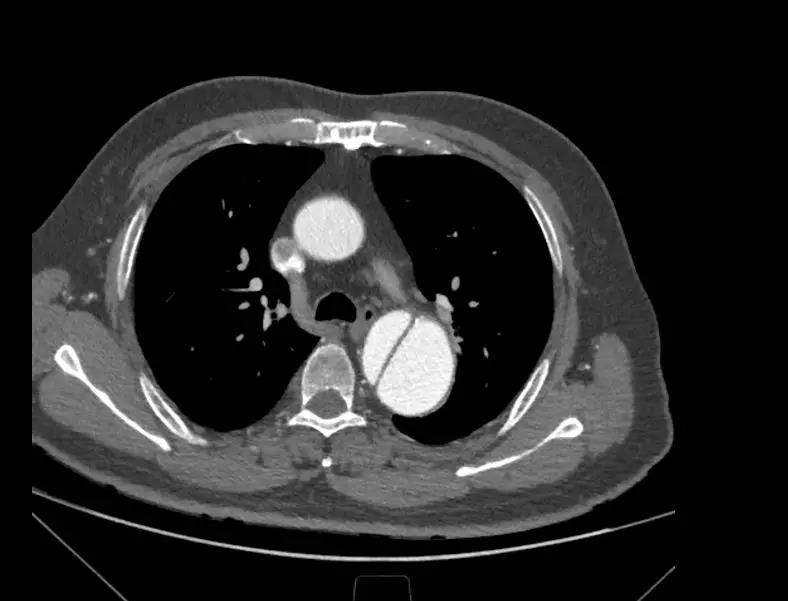

6月25日,中国医学科学院阜外医院向大会现场直播了一台采用先健新型主动脉支架系统进行的手术。手术由舒畅教授担任主要术者,接受手术的患者为一名65岁男性,入院后经CTA检查确诊为“慢性B型主动脉夹层”,夹层破口紧邻左锁骨下动脉,病变累及到两侧髂总动脉,主动脉真腔严重受压,假腔巨大,近端锚定区严重不足,病情十分危重。

术中通过DSA造影显示:主动脉夹层破口位于左锁骨下动脉近端,真腔压闭。舒畅教授通过左锁骨下动脉预置Longuette™裙边支架,释放 Ankura™ Pro主动脉主体覆膜支架,封堵破口后通过裙边支架显影点准确定位,释放裙边支架,凭借着舒畅教授精湛的手术操作和器械的优异性能,手术过程非常顺利,胸主动脉支架释放良好,患者的主动脉夹层破口封闭良好,左锁骨下动脉释放的裙边支架血流通畅,没有内漏发生。由于患者远端真腔较小,为了保证远端的血流,植入了一个cuff支架,造影显示远端真腔打开良好。

(图:术前造影)